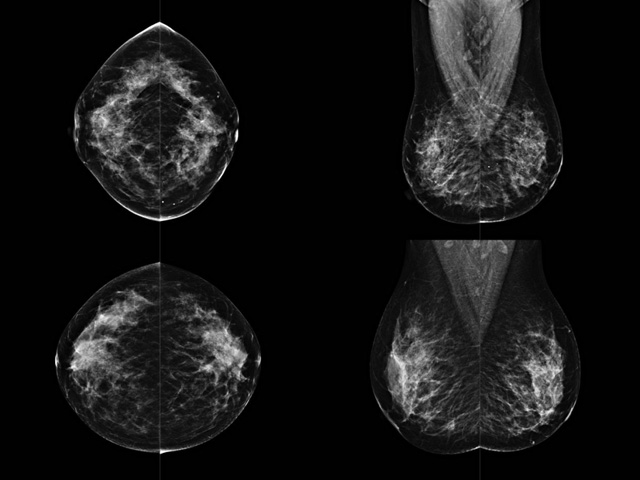

乳房檢查時候要注意一些細節,需要更深入的了解這樣才能使檢查更準確。乳腺DR是乳腺癌的篩查診斷工具設備。是乳房方面檢查的重要影像方法。它可以臨床檢查出早期的乳腺癌。可以判斷良性惡性。因為它可以檢查出早期的病變。對良性惡性檢查的準確率達到90%以上。發病高峰年齡為45歲到54歲。50歲檢查出來乳腺癌病患,可以讓死亡率下降3成。所以30-40歲女性每年做一次乳腺DR檢查。40歲以上就一年兩次。如果家族史有乳腺癌的30歲以下也需要做檢查。清晰顯示乳腺各層組織嚴重的乳腺增生,乳腺炎,乳腺外傷也建議1年檢查一次。極大提高了早期乳腺癌的敏感度和診斷率。

大角度、高質量的乳腺檢查,可以讓女性帶來身體健康安全。為醫生提供了高清影像數據。乳腺檢查時候各個部位影像顯示出來。白色乳腺導管跟纖維結締組織。模糊的是脂肪。病變一般是不透明的白色。有需要放大來檢查。乳腺DR沒有重疊偽影。輻射劑量更少。因為乳腺癌發病每年都有所提高,對女性都造成了嚴重的身體健康危害。早做檢查早治療是不可忽視的舉措。可以大大的降低死亡率。保證身體健康。一般檢查避開經期,來完7天左右是最佳的檢查時間。絕經的女性就沒有要求。孕婦不參加乳腺DR檢查, 6個月內準備妊娠的婦女也不宜行此檢查。